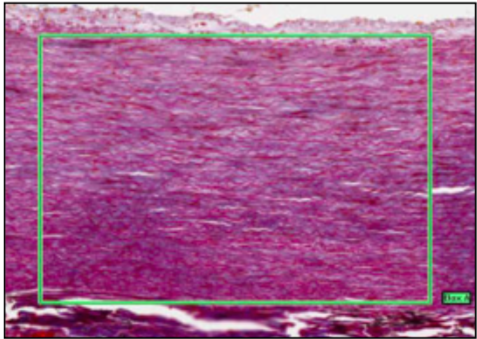

ELASTIC ARTERY (WITH MALLORY’S STAIN)

- elastic - red / collagen & muscle - blue

- = aorta and GT vessels close to heart

- medial layer thick w/concentric sheets of elastic interspersed w/smooth muscle

- as vessels large - contain own blood supply vasa vasorum

at top = intima then internal elastic lamina, then vascular endothelial cells on BM